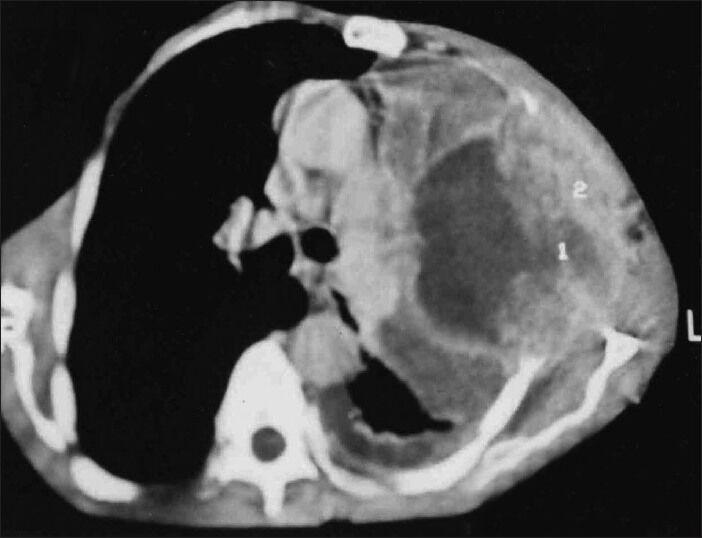

Biphasic pulmonary blastoma: An unusual presentation with chest wall, rib, and pleural involvement.

Lung India. 2014 Jan;31(1):87-9. doi: 10.4103/0970-2113.126002.